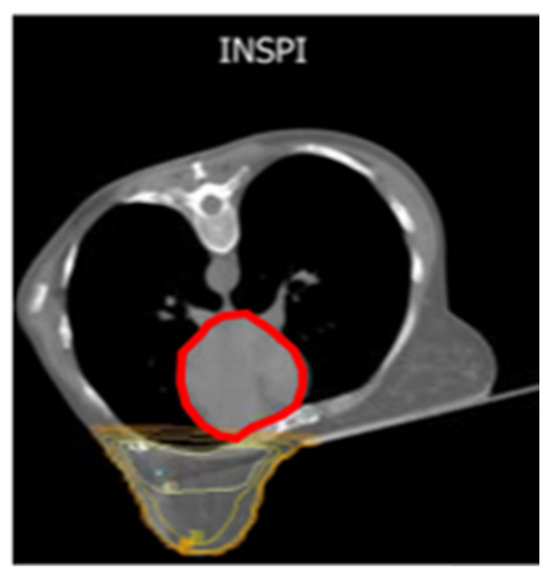

The Prone-Position Whole Breast Irradiation Paradox: Where Do We Stand? A Comprehensive Review

by Chris Monten, Ilaria Benevento, Antonietta Montagna, Edy Ippolito, Paola Anselmo, Luciana Rago, Barbara D’Andrea, Angela Solazzo, Antonella Bianculli, Raffaele Tucciariello, Giammaria Fiorentini, Vito Metallo, Simone Salvago, Carmen Santoro, Anna Vallario and Grazia Lazzari

Over the past two decades, interest in prone-position whole breast irradiation (WBI) as an effective and practical alternative to supine treatment has been growing a lot. Although solid scientific data has provided evidence of substantial dosimetric benefit with decreased toxicity, there is still [...] Read more.

Over the past two decades, interest in prone-position whole breast irradiation (WBI) as an effective and practical alternative to supine treatment has been growing a lot. Although solid scientific data has provided evidence of substantial dosimetric benefit with decreased toxicity, there is still conflict in the radiotherapy community over whether to adopt prone-position WBI as a valid alternative to supine radiotherapy (RT) in routine clinical practice. A large number of prone trials have been conducted to assess and address concerns related to prone treatment in large and pendulous breasts and in left and right breast cancer (BC), nodal irradiation, and its reproducibility with deep inspiration breath hold (DIBH) delivery with photons or protons. Appropriate atlases have been defined to improve prone nodal irradiation. Additionally, more comfortable customized immobilization couches have been constructed to permit IMRT beams and VMAT arrangements with modern LINACs. Although our search in literature databases shows a growing body of evidence from the past two decades on this issue, prone WBI is still underused. Given the paradox of the advances and benefits of this positioning and the lack of drive in the radiotherapy community towards its clinical implementation, the purpose of this comprehensive review is to evaluate the true advantages of this position in real life and contextualize it in scenarios like large breasts, left-sided breast cancer, and nodal irradiation to encourage its implementation in clinical practice. Full article

Show Figures

Figure 1